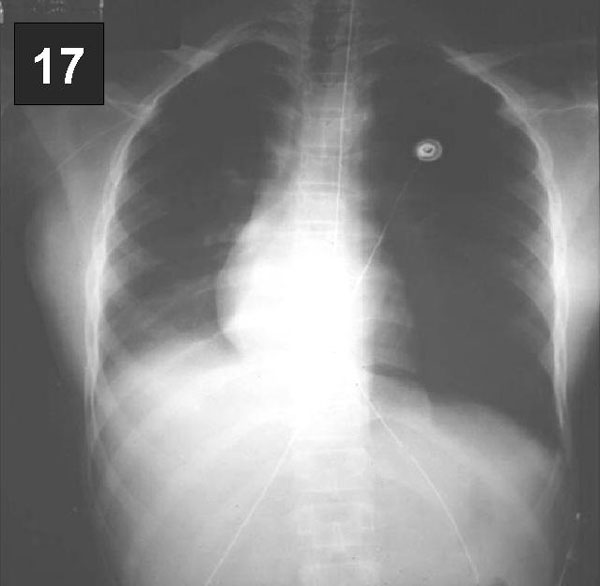

PLACA 17